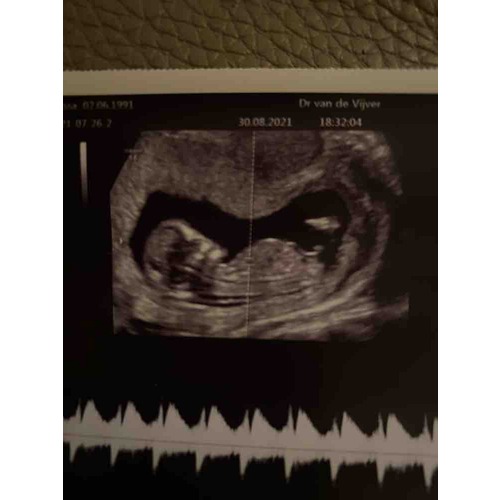

Iemand een idee? Verloskundige vond het een jongen tijdens de echo (als ze alleen naar de nub kijkt) maar foto’s vinden we beide best verwarrend.. we kunnen namelijk beide zien. Wat zeggen jullie?